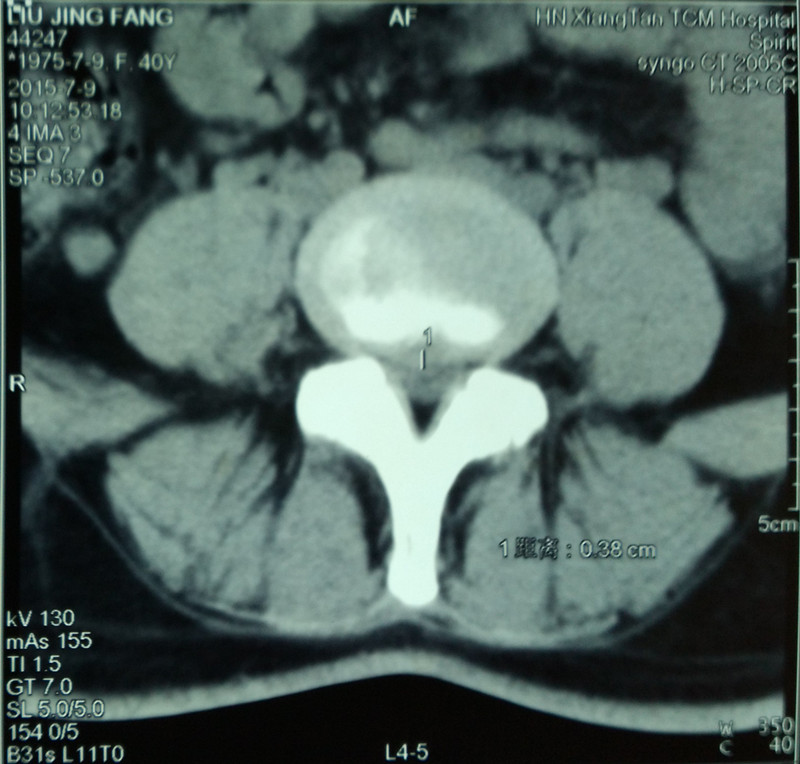

近日,王女士因右下肢放射痛到湘潭市中醫(yī)醫(yī)院脊柱骨科門診就診,并訴5年前有左下肢曾有明顯麻痛史,經治療后一直未復發(fā)。醫(yī)生根據(jù)CT檢查所提示的L5/S1椎間盤明顯突出并鈣化,L4/5椎間盤突出并不明顯,很容易診斷為L5/S1椎間盤突出癥。但結合病史、主訴、癥狀及體征仔細分析,可明確診斷為L4/5椎間盤突出癥,而5年前左下肢疼痛原因才是L5/S1椎間盤突出癥。